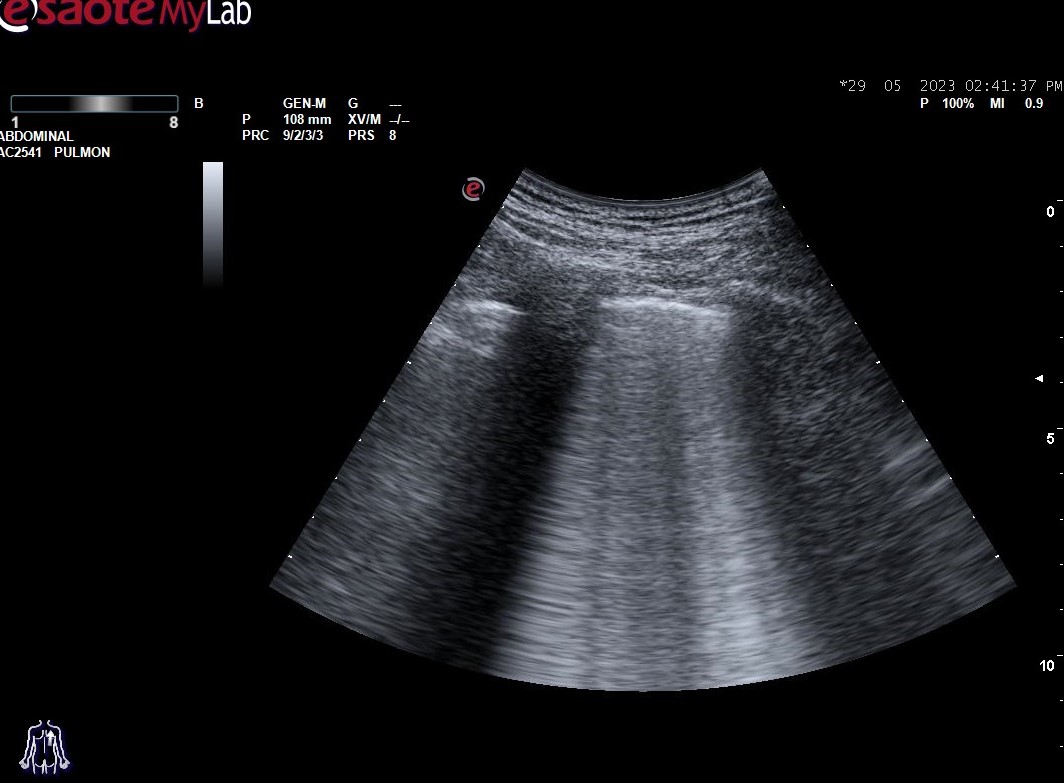

Hallazgos ecográficos: derrame pleural bilateral y abundantes líneas B (más de 3 por espacio intercostal) en ambos 1/3 medios inferiores bilaterales (adjuntamos imágenes).

En la ecografía pulmonar observamos unos patrones ecográficos (normal, deslizamiento pleural, líneas A, líneas B, derrame pleural y consolidación pulmonar). Realizando una serie de preguntas dicotómicas sobre estos patrones ecográficos se establece un algoritmo (protocolo BLUE) que permite establecer con alta sensibilidad y especificidad la causa de la disnea mediante un árbol de decisión.

Aplicando dicho protocolo establecemos un diagnóstico ecográfico de presunción de Edema Agudo de Pulmón/Insuficiencia cardíaca.